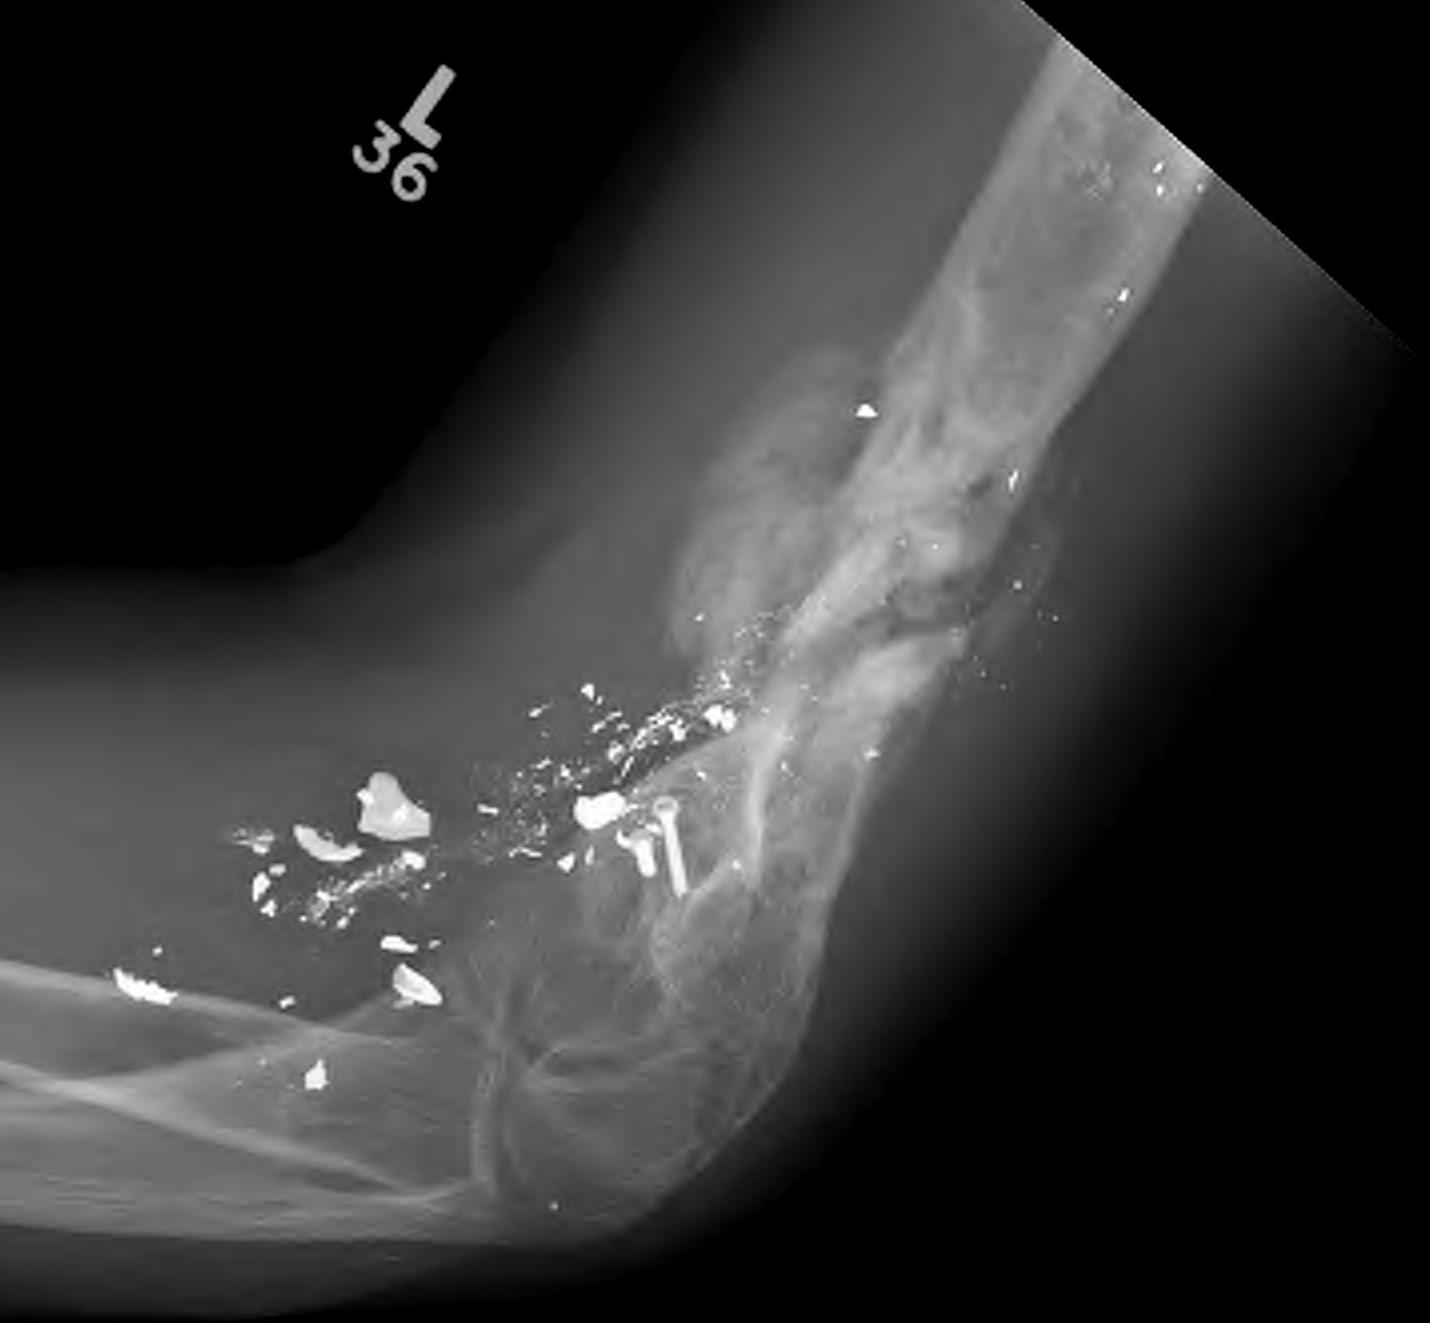

Gunshot wound elbowGunshot wound elbow 2